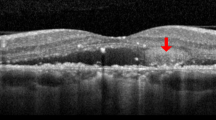

Spironolactone reduces CNV activity in refractory nAMD

Twenty patients with nAMD presenting with refractory intra- or subretinal fluid despite monthly intravitreal injections of anti-VEGF (≥12 months anti-VEGF treatment, ≥6 months refractoriness despite monthly injections, using the same anti-VEGF molecule (Aflibercept in 13 eyes/Ranibizumab in 8 eyes), ≥350 µm on thickest A-scan on optical coherence tomography (OCT)) consented to participate to a prospective pilot study. Refractoriness was defined as no reduction in exudative signs during the last 6 months. In addition to monthly injections of anti-VEGF during the 6-months study period, continuing with the same anti-VEGF molecule as used during the ≥6 months before inclusion, they were prescribed adjuvant oral spironolactone (25 mg/day week 1, 50 mg/day until Month 3, 25 mg/day until Month 4, 0 mg until Month 6). In 21 eyes of 20 patients with refractory nAMD (13 females, mean age 76.3 ± 7.7 (SD) years received 37.2 ± 17.1 (mean ± SD) anti-VEGF injections given over a mean period of 46.0 ± 19.8 (SD) months prior to study enrollment), statistically significant changes in structural outcome measures, maximal at Month 3 compared to baseline, were observed on spectral domain OCT (SD-OCT) at various time points during spironolactone treatment (Fig. 1). The effect was seen in central retinal thickness (p = 0.011) and volume (p = 0.012), in the foveal thickness (p = 0.039), the thickest cystic changes (p = 0.040), and subretinal fluid (p = 0.014), which all quantify macular edema (Table 1 and Fig. 1, using paired Wilcoxon signed-rank tests). The improvements observed on SD-OCT were lost after stopping the spironolactone at Month 4 although anti-VEGF injections alone were continued (Table 1 and Fig. 1). Individual treatment responses are imaged by thickness maps and a selected B-scan OCT for baseline, 3 and 6 months (horizontal line) for all eyes, obtained with the follow-up mode of the Spectralis OCT (Heidelberg Engineering, Germany) (Supplementary Figs. 2–4). There was a high heterogeneity in the patient’s response to the treatment, with about 50% showing a reduction of fluid at 3 months that could be attributable to spironolactone treatment, which without a control groups remains to be confirmed by a randomized controlled study. Adjuvant oral spironolactone therapy was subjectively well tolerated by most patients. However, two (10%) of them discontinued the drug after 2 months due to increased plasma potassium levels. On the basis of an intention-to-treat approach, these patients were maintained in the analysis.

Clinical results. a Relative changes in subretinal thickness (SRF, µm) measured with Spectralis OCT during the study period, month 0 (M0) to month 6 (M6). SRF thickness is significantly reduced as compared to M0, at M1 (p = 0.012), M2 (p = 0.040), M3 (p = 0.014), M4 (p = 0.024). b Relative change in central retinal thickness (CRT, µm) automatic values with Spectralis OCT during the study period, month 0 (M0) to month 6 (M6). CRT is significantly reduced as compared to M0, at M3 (p = 0.011), M4 (p = 0.007), and M5 (p = 0.028). At each time point (Month, M), the data have been summarized using box and whisker plots, the upper and lower 95% CIs (confidence interval) are marked with the whiskers, the box represents the interquartile range, and the median is represented by the bold horizontal line bisecting the box. Paired Wilcoxon signed-rank tests were used. *p < 0.05